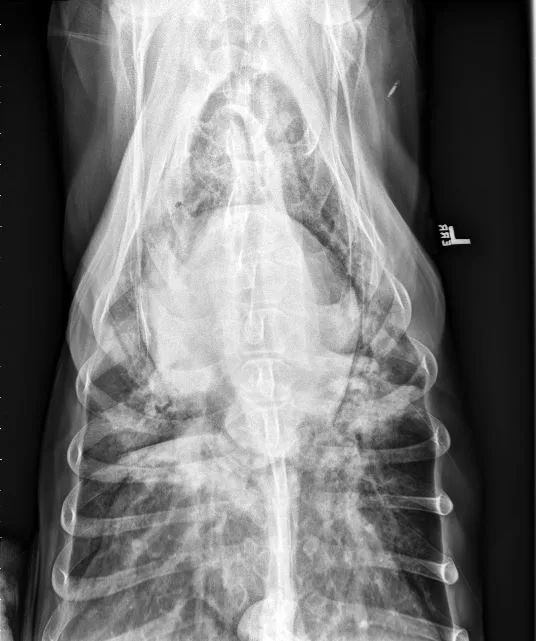

FIGURE 11 Right lateral (left) and VD (right) projections of a crossbreed dog with tricuspid valve dysplasia. The cardiac silhouette has increased width, and the regions of the right atrium and ventricle show roundness. The cardiac apex is displaced to the left secondary to right-sided enlargement (right). The caudal vena cava (arrowheads) is dilated, and there is loss of abdominal serosal detail secondary to increased systemic venous pressures and right-sided CHF, respectively. The pulmonary vasculature is small secondary to pulmonary hypoperfusion (given significant regurgitation across the tricuspid valve and decreased forward blood flow). VHS, VLAS, M-VLAS, and VRHi collected from the right lateral view are 12.3, 2.3, 2.7, and 3.8, respectively. Images courtesy of Bruna Del Nero, DACVIM (Cardiology)